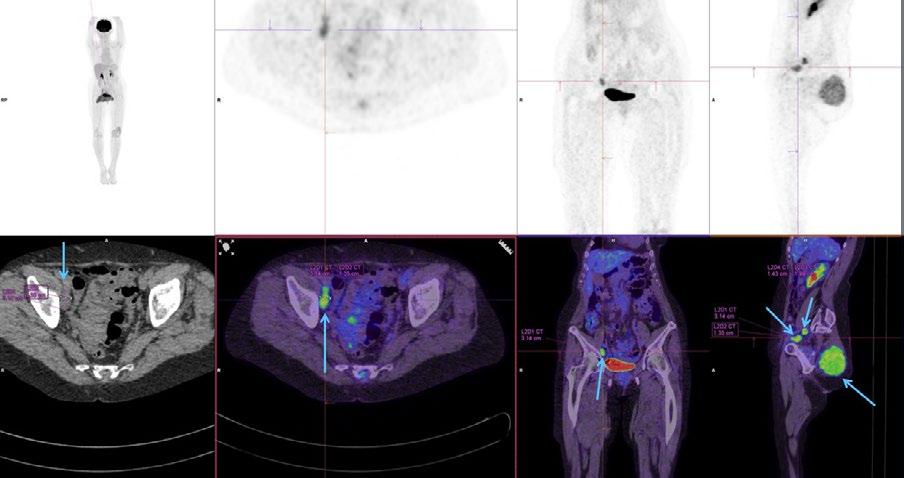

Issuu converts static files into: digital portfolios, online yearbooks, online catalogs, digital photo albums and more. Sign up and create your flipbook.